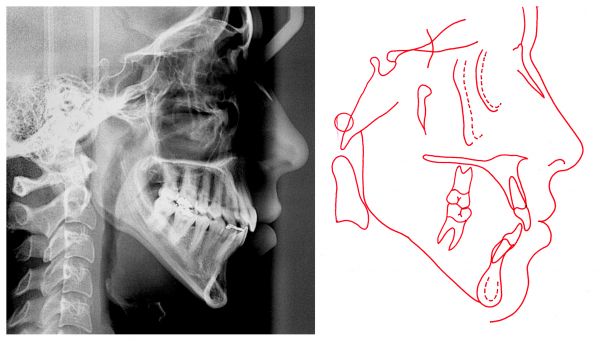

Radiografia inicial

Telerradiografia e traçado final